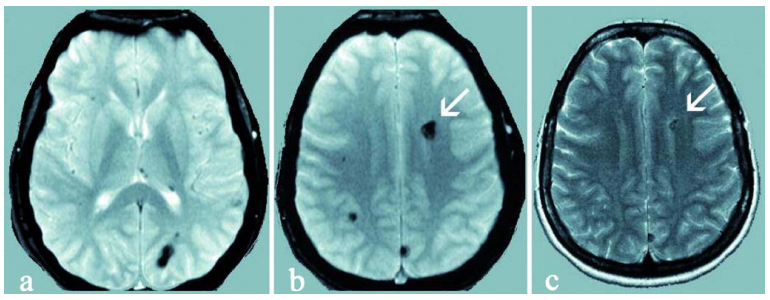

来自母亲的遗传

很明显,楠楠所患的是多发性海绵状血管瘤,这让医生不由得开始怀疑,这个3岁小女孩身上可能存在家族遗传基因。果然,在对楠楠母亲进行基因检测后,医生发现楠楠和母亲体内都藏着一个名为CCM1基因的新发突变。而在楠楠母亲的核磁上,也发现了多个海绵状血管畸形的小病灶,但楠楠母亲至今并未出现任何症状。